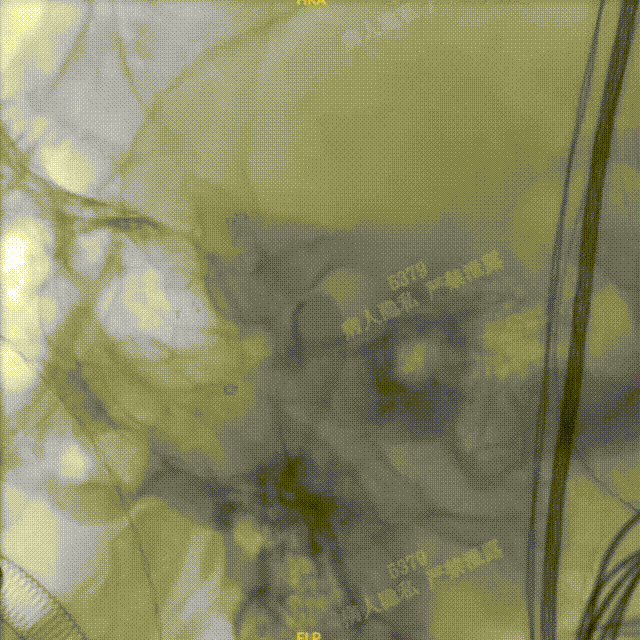

术中DSA造影:右侧颈内动脉侧位及3D造影,显示右侧颈内动脉后交通段动脉瘤。

术中DSA造影:左侧颈总动脉3D造影及左侧锁骨下正位造影。